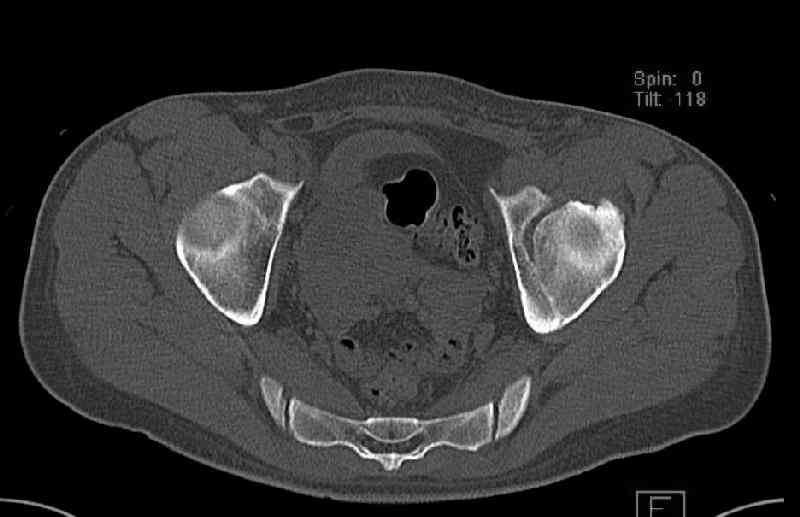

The last two images from the 3-D CT scan certainly makes the fracture look worse than the plan radiographs.

Some more images. Does it help to guess which part of the acetabulum is displaced?

Normal appearing SI joints and a healed posterior column limb... my bet's on caudal segment displacement.